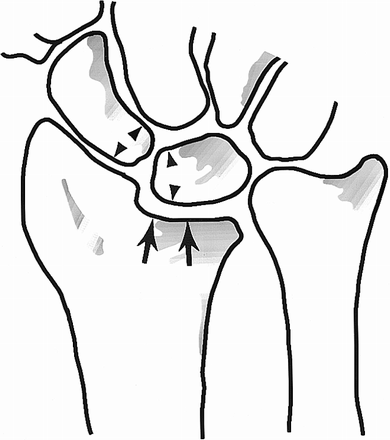

В очередной раз здравствуйте, уважаемые посетители нашего славного форума.<br /><br />Перед созданием очередного поста, неизменно посвященного вопросам травматологии и ортопедии, я задумался над его тематикой. Множество вопросов было поднято ранее, сделаны небольшие обзоры литературы, некоторые статьи переведены и адаптированы для русскоязычного пользователя.<br /><br />Но, кто является потребителем данной информации? Иногда создается впечатление, что форум стал пустынной обителью поисковых роботов...<br /><br />Может эта тема вызовет интерес, учитывая огромную распространенность подобного вида травмы? Каждый студент или молодой доктор-травматолог начинает изучение и погружение в специальность с самых частых и типичных случаев. <br /><br />Переломы дистального метаэпифиза лучевой кости относятся к наиболее частому виду травм в популяции и составляют до 15% от всех переломов костей конечностей. Большая часть из этих переломов - переломы со смещением и требуют активной тактики. При консервативном лечении (закрытой репозиции) только в 27-32% сохраняются приемлемые осевые и анатомические взаимоотношения, что имеет соответствующее отражение на качестве жизни пациентов. А поскольку этот вид травмы затрагивает людей как молодого, так и старшего возраста актуальность темы не снижается, а возрастает. <br /><br />В своем небольшом сообщении я бы не хотел сильно распространяться и пропагандировать какой-либо из методов лечения. <br /><br />Ограничимся перечислением и примерами наиболее характерных вариантов травмы:<br /><br />1) Pouteau - Colles: экстензионный перелом дистального метаэпифиза лучевой кости. Возникает от непрямого механизма травмы при падении на ладонь, находящуюся в положении тыльного сгибания, дистальный отломок смещается в тыльную и лучевую сторону, вызывая характерную «вилко-» или «штыкообразную» деформацию предплечья<br /><br />